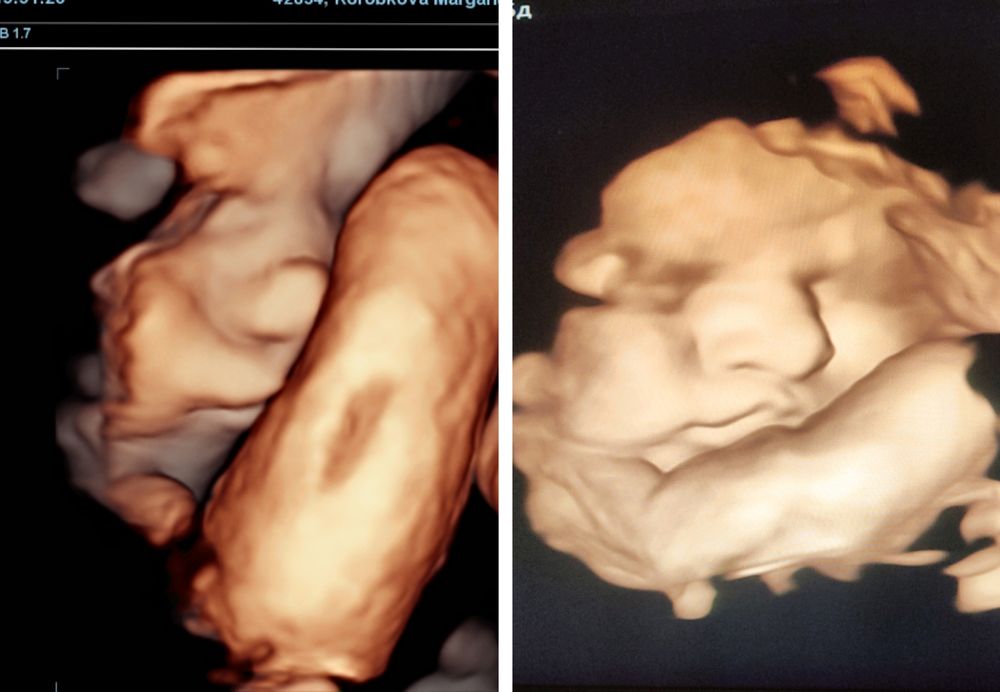

5. Ребенок: что-то кажется мне, что будем мы больше. Или родимся раньше пдр. На 34 неделе делали скрининг, вес был 2.3, пару дней назад (35+5) делали УЗИ в ЖК, показали 3д картинку, так там такие щеки выросли) вес уже 2.6

Слева 34, справа 35+5. Мне кажется, что похожа на меня, правда вот нос какой-то большой) наверно, папин. Врач а ЖК сказала "ой на маму похожа, и нос мамин"😅